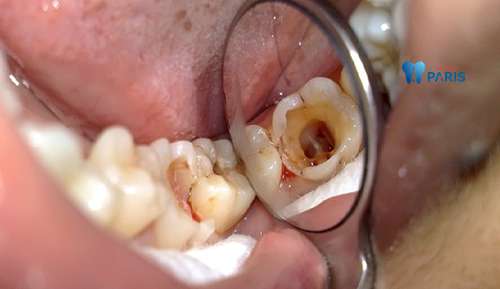

Răng bị sâu lớn có trám răng được không? Để biết trám răng sâu lớn được hay là không bạn nên tham khảo chi tiết qua bài viết sau đây…

Trám răng là biện pháp hiệu quả đối với những tình trạng sâu răng. Tuy nhiên, đối với những vết sâu lớn thì trám răng có phải là biện pháp…